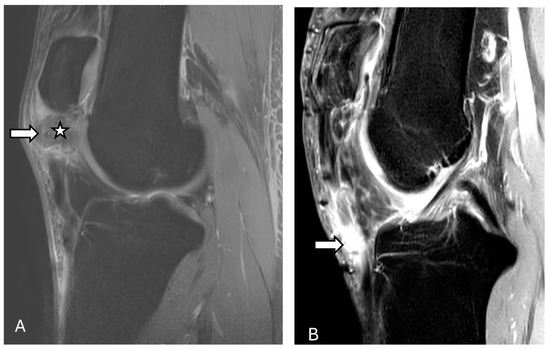

3.2. Chronic Patellar Instability and Malalignment